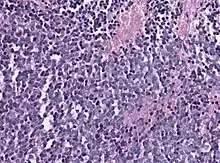

Biopsy is required for diagnosis. Pineoblastomas appear as high grade, highly cellular, small blue cells histologically. Features of aggressive malignancies can be seen, like high nucleus-to-cytoplasm ration, poorly differentiated cells, high mitotic activity, and necrosis.[13][3] Homer Wright, or neuroblastic, and Flexner-Wintersteiner, or retinoblastic, rosettes can also be seen. In contrast to other masses of the pineal gland, pineocytomatous rosettes are not present.[13] Immunohistochemistry staining will reveal neuronal, glial, and photoreceptor marker positivity. This includes synaptophysin, neurofilament protein, and CRX, a specific pineal or retinal marker, positive staining.[13][7]